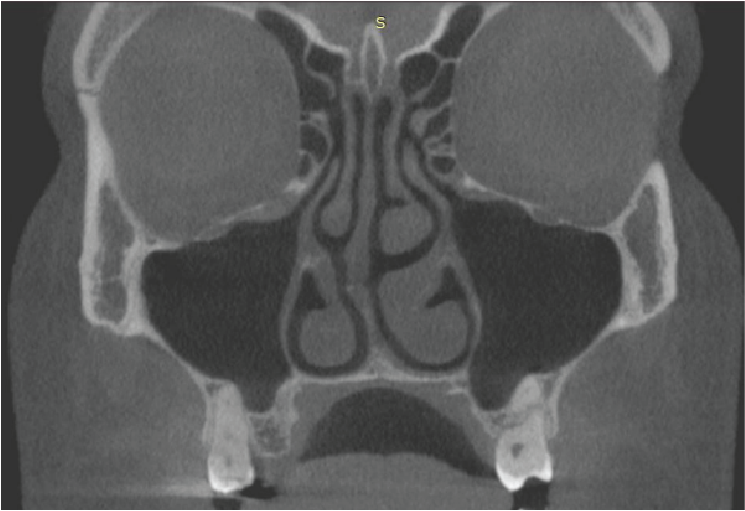

There is coverage of all the nasal cavities and paranasal sinuses apart from the most superior parts of the frontal sinuses. There is deviation of the nasal septum to the right side, with a bony spur projecting into the right middle meatus. Asymmetries of the turbinate bones are associated with this, with relatively larger turbinates on the left side and with a paradoxical curvature of the left middle turbinate. No mucosal disease in the nasal cavities. The maxillary antra are aerated normally apart from very limited mucosal thickening at the medial part of the antral roof on the right side, close to the natural ostium. The ostia are patent bilaterally (image 1). Other paranasal sinuses are normally aerated. The deviation of the nasal bone anatomy has an effect on the width of the frontal recess (the drainage channel of the right frontal sinus leading into the ostio-meatal complex), but it is patent. Overall, the ostio-meatal complexes are patent bilaterally and the nasal cavity and paranasal sinus health is clear.

Image 1

Coronal cross-section through the maxillary antra and their ostia